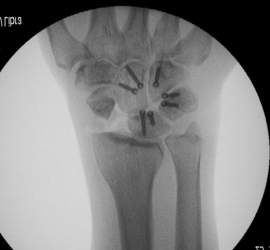

FRATURAS DO ESCAFOIDE NO CURSO SKYMEDICAL – NOV. 2018

As Fraturas do Escafoide no Curso Avançado de Trauma de Membro Superior SKYMEDICAL 8 e 9/NOV/2018. Participou como formador nesta edição do Curso SKYMEDICAL com uma palestra sobre fraturas do escafoide e lecionando a trabalho prático sobre osteossíntese do escafoide com e sem enxerto ósseo.

Artrodese intra-Carpica – Curso Medartis – Maio de 2018

Artrodese intra-Carpica – Curso Medartis – Maio de 2018 O Curso Avançado da Mão e Cotovelo Medartis já vai na 3ª Edição. Realizado em 12/5/18 no Instituto Superior de Ciências da Saúde Egas Moniz, na Caparica, no dia. Lecionou o tema teórico e as aulas Práticas das Artrodeses intra-Carpicas.

Fracturas do Rádio Distal e Artrodeses do carpo – palestras em AOTrauma Curso Avançado – Mão e Punho, 05 a 07 de Novembro de 2015 Ericeira

A Marca AOTrauma realiza com regularidade cursos práticos avançados de Cirurgia da Mão. Tem feito parte da Faculty com apresentação de Temas Teóricos e como monitor nos exercícios práticos. No atual Curso coordenou os exercícios de artrodeses radio-cárpicas (total ou parcial) e proferiu as palestras – Fracturas do Rádio Distal […]